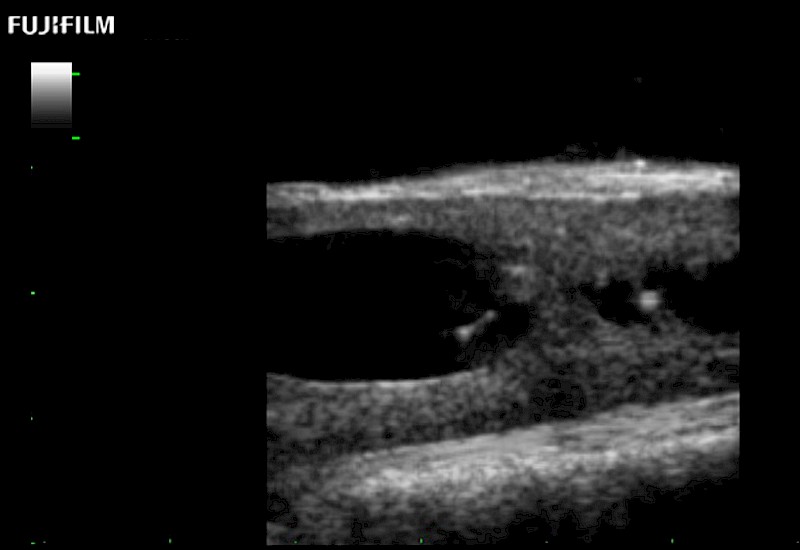

Exclusive 10mm side‐fire linear array transducer with 2.87mm diameter is ideal for real‐time visualization through and behind structures and instant, scalable definition of anatomy and vascularity including the ability to delineate and define tumor margins.

Main Specifications: